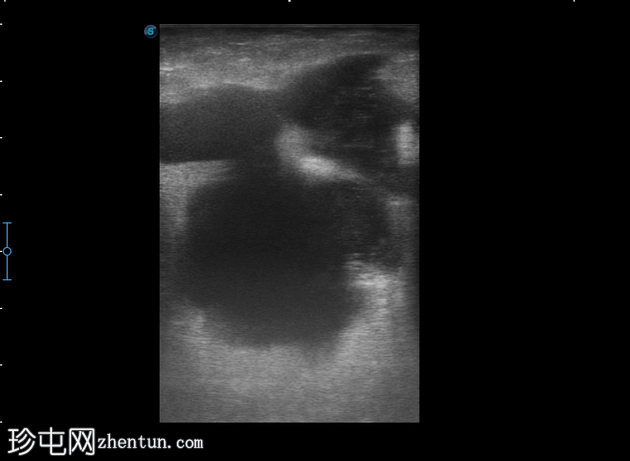

4-10点钟平面

深表探头

在右前外侧肛周区域(具体位置为10-11点钟方向,紧邻肛壁)观察到一个边界清晰、大小约为5 x 5厘米的低回声病变。病变壁不规则,后部回声增强。病变内部回声提示可能存在肛周脓肿。

在此阶段,未见内部瘘管或与肛管的交通。此外,未检测到明显的病灶周围血管或气体灶。为了更好地评估病变的定位和范围,除了浅表探头外,可能还需要深层探头。